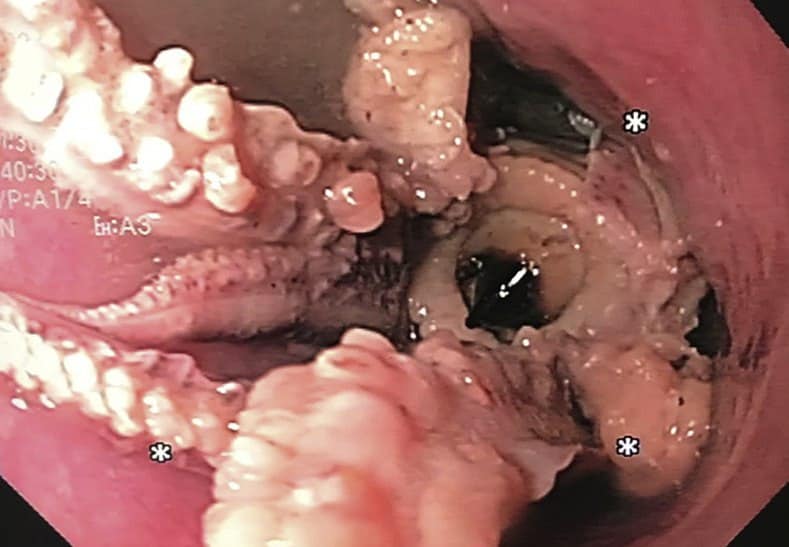

Khi tiến hành kiểm tra đường tiêu hóa, các bác sĩ nhận thấy có một dị vật mắc kẹt giữa đoạn thực quản và dạ dày người đàn ông. Hình ảnh từ camera nội soi cho thấy, sinh vật có 8 xúc tu mắc kẹt trong thực quản người đàn ông, khiến anh không thể nuốt được thêm bất kì loại thức ăn nào.

Lúc đầu, các bác sĩ đã thử dùng “kỹ thuật đẩy” nhưng con bạch tuộc không có dấu hiệu dịch chuyển, nếu tiếp tục sẽ dẫn đến nguy cơ làm vỡ thực quản do áp lực đẩy quá lớn. Vì vậy, họ đã cố gắng đưa ống nội soi qua con bạch thuộc vào dạ dày và sau đó uốn ngược lại, đẩy lên họng người đàn ông. Sau đó, các bác sĩ đã phải dùng kẹp để gắp sinh vật biển này ra khỏi thực quản.